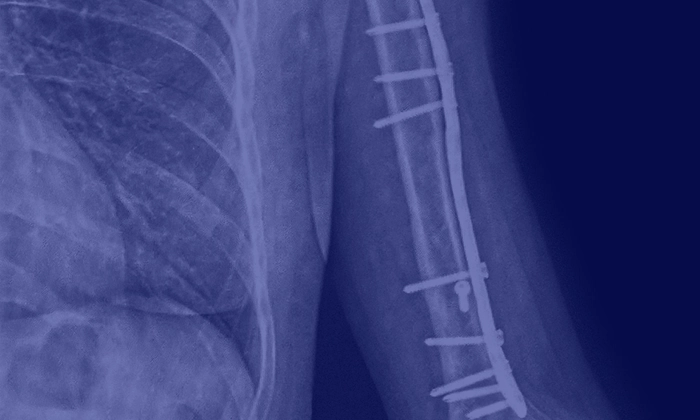

Остеосинтез — ефективна методика лікування складних переломів. Вона полягає у фіксації фрагментів кісток в анатомічно правильному положенні. Для цього використовуються спеціальні металоконструкції — зовнішні чи внутрішні. Пластини, стрижні, спиці, гвинти та інші імпланти дозволяють зафіксувати фрагменти кістки та забезпечити зрощення у правильному положенні.

Металоостеосинтез — це операція, в якій хірург-ортопед-травматолог складає уламки ушкоджених кісток і фіксує їх у правильному положенні. Подальше лікування полягає у стимулюванні природних регенеративних процесів до повного зрощення фрагментів кістки між собою.

Фрагменти кісток вручну встановлюються на правильні місця. Після виконання відкритої репозиції їх фіксують металевими конструкціями.

Під час операції лікарі використовують рентген-контроль, який дозволяє переконатися в правильності встановлення уламків. Після завершення процедури розріз ушивають та накладають пов’язку. За необхідності кінцівку можуть додатково фіксувати гіпсом чи ортезом, хоча частіше в цьому немає потреби.